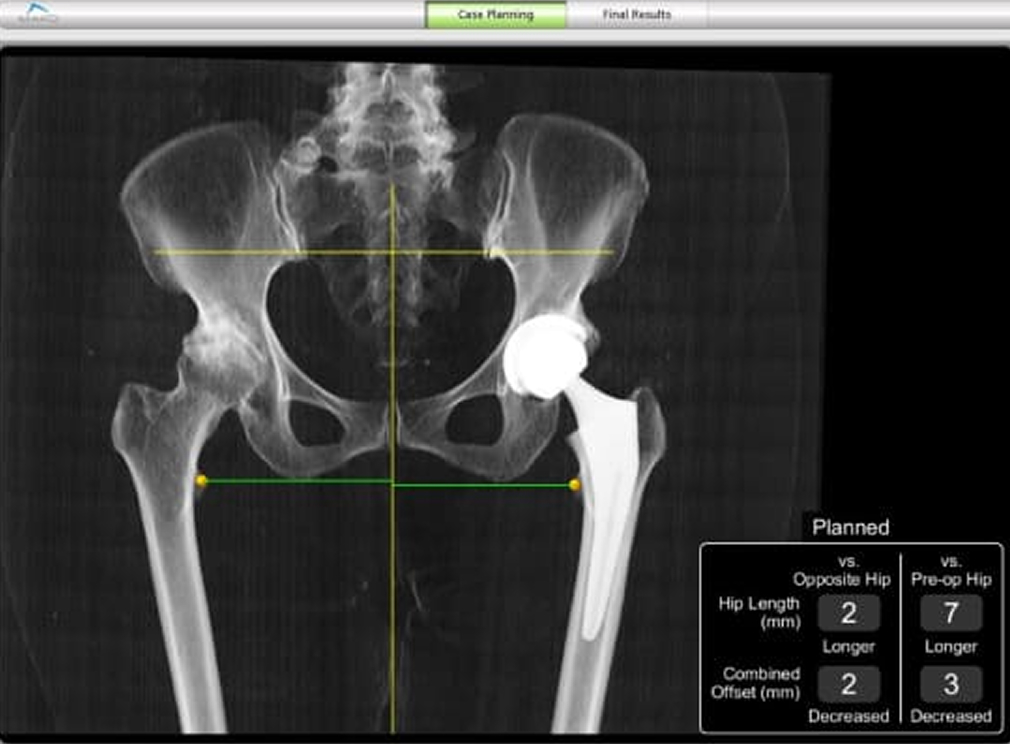

CT画像をもとに作成された三次元画像で手術計画を行い、インプラントサイズ、設置位置、削る深さや角度を決定します。 THAでは骨盤をリーミングしてカップ設置する際、TKAやUKAでは骨切りを行う際にロボティックアームが術者をサポートします。 術前計画にはない角度や深さを削ろうとすると制御がかかり、ロボティックアームが止まるシステムになっています。 身近なものに例えると車の自動ブレーキのようなもので、計画通りの手術を行うことが可能となりました。

• CT画像をもとに作成した三次元像を用いた手術計画

• 術後のレントゲン像